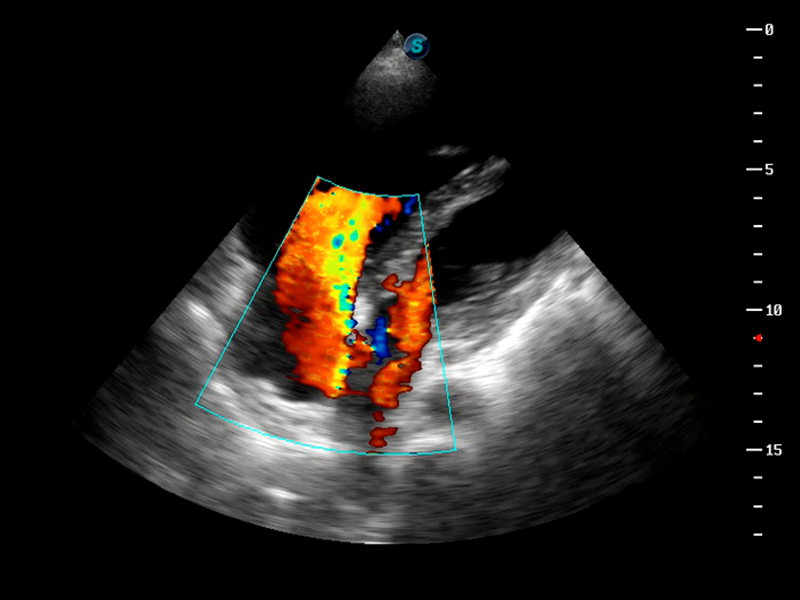

S9便携式彩色多普勒超声诊断仪是乐玩lewin国际研发的高端便携彩超设备,外观设计新颖、产品性能卓越。S9在便携超声领域采用了突破传统的触摸屏交互设计,并以先进的软件硬件技术和设计理念,为您带来清晰的图像质量、稳定的工作性能和便捷的操作体验。

AutoC智能血流追踪